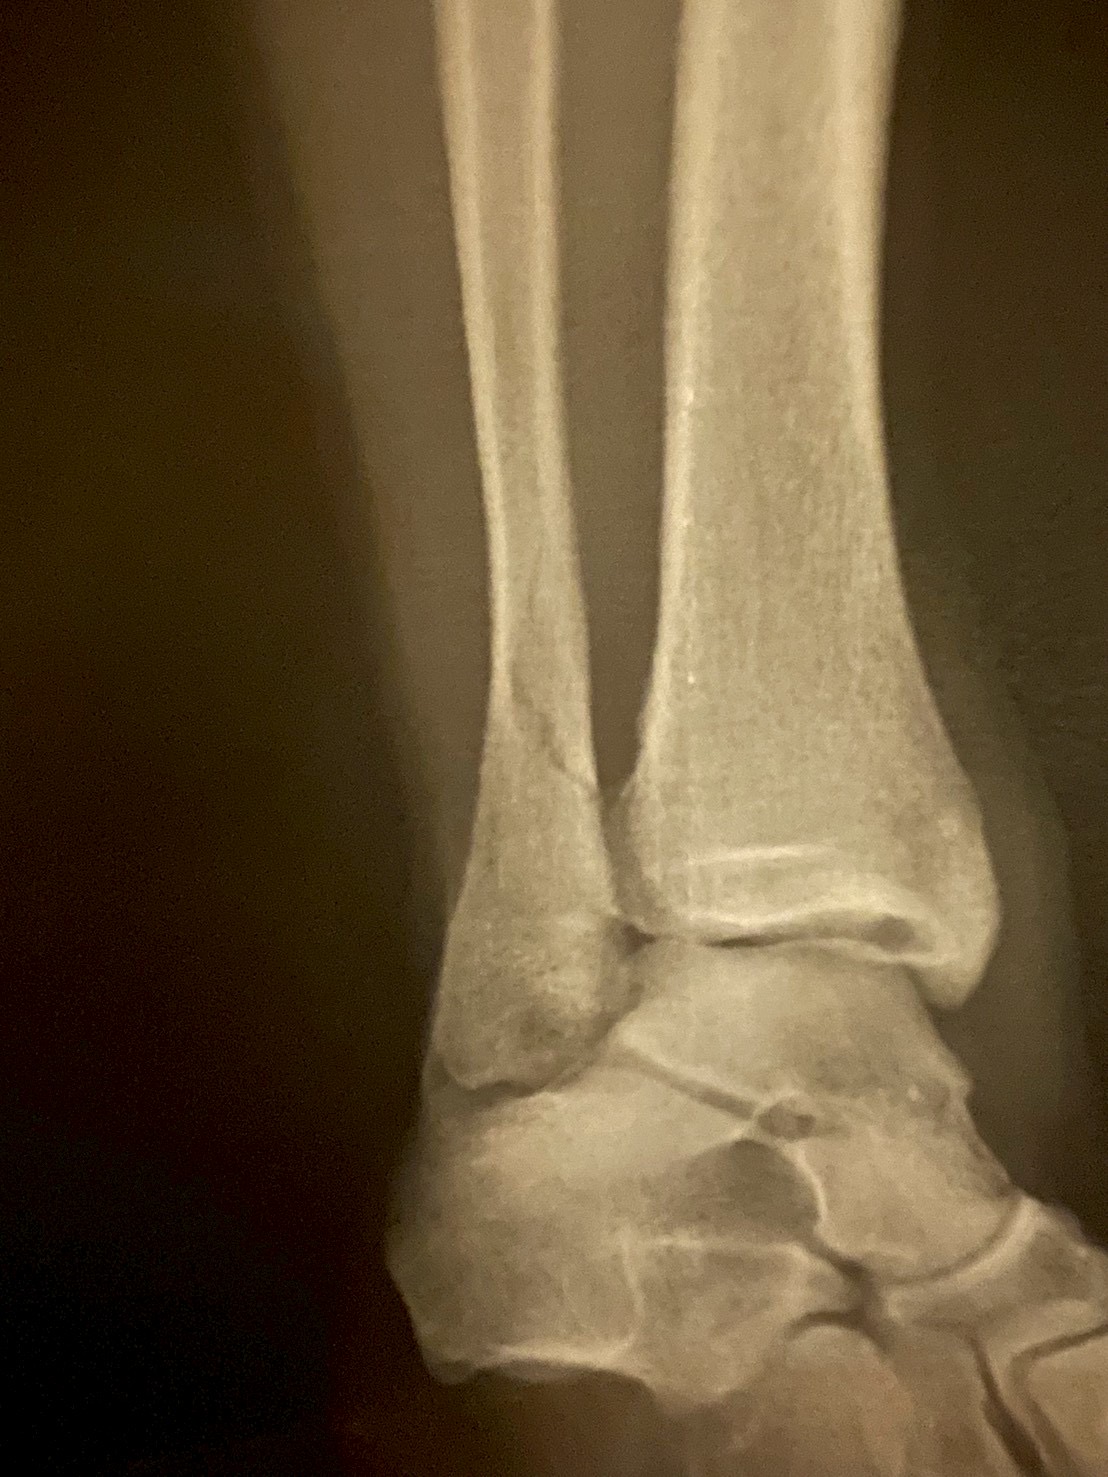

GB練中に骨折

武者先でのまさかの怪我でした。

まずあの時介抱していただいた明学のマネージャーの方ありがとうございました。

ご迷惑をおかけいたしました。

病院で全治約半年を告げられ絶望しました。

自分の成長を実感している今

関東で大きな刺激を受け、たくさんのインプットをした今

なぜこのタイミングなのかと何度も何度も思いました。